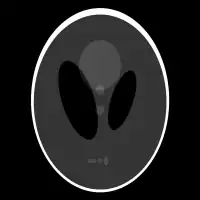

| Fantasma de Shepp-Logan; Transformada de Radon; y Transformada de Radon inversa | ||

Existe un algoritmo inverso de la transformada de Radon computacionalmente eficiente para el caso bidimensional llamado retroproyección filtrada. Primeramente consideremos el operador adjunto de :

lo que significa que la imagen original puede ser recuperada del 'sinograma' aplicando un filtro rampa (sobre la variable ) y entonces retroproyectando. Como que el paso de filtrado puede ser implementado de forma eficiente (mediante técnicas de procesamiento digital de señales) y la retroproyección no es más que una acumulación de valores en los píxeles de la imagen, resulta un algoritmo altamente eficiente, por lo que se trata de un algoritmo ampliamente usado.